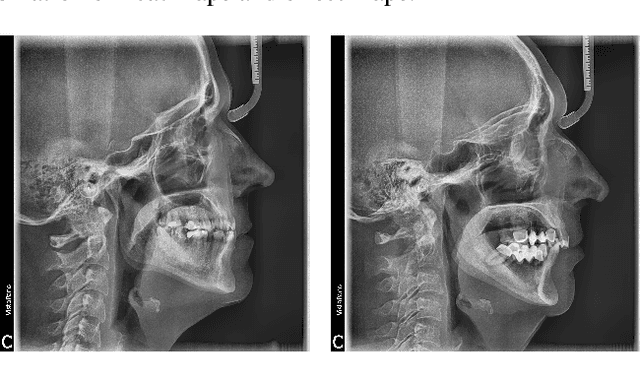

Abstract:Convolutional neural networks (CNNs) are used in many areas of computer vision, such as object tracking and recognition, security, military, and biomedical image analysis. This review presents the application of convolutional neural networks in one of the fields of dentistry - orthodontics. Advances in medical imaging technologies and methods allow CNNs to be used in orthodontics to shorten the planning time of orthodontic treatment, including an automatic search of landmarks on cephalometric X-ray images, tooth segmentation on Cone-Beam Computed Tomography (CBCT) images or digital models, and classification of defects on X-Ray panoramic images. In this work, we describe the current methods, the architectures of deep convolutional neural networks used, and their implementations, together with a comparison of the results achieved by them. The promising results and visualizations of the described studies show that the use of methods based on convolutional neural networks allows for the improvement of computer-based orthodontic treatment planning, both by reducing the examination time and, in many cases, by performing the analysis much more accurately than a manual orthodontist does.